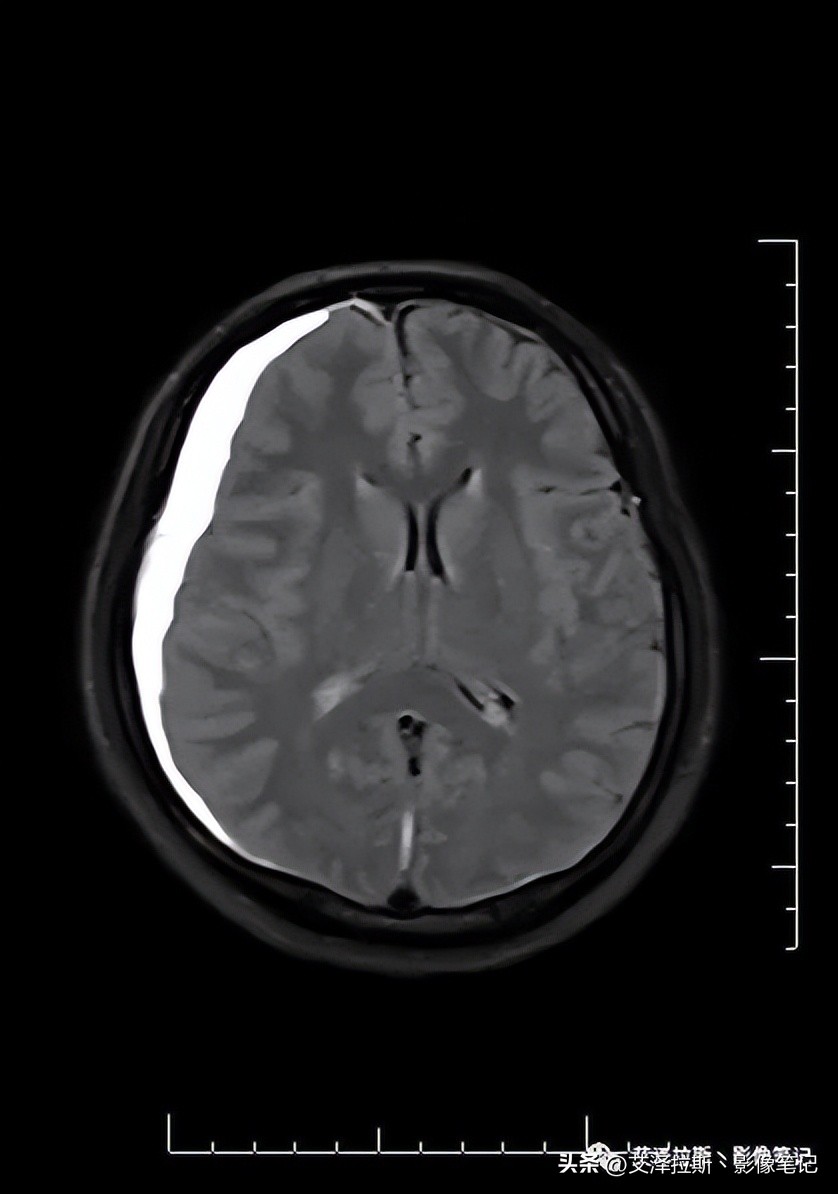

图1 T2WI

图1-4显示右侧硬膜下血肿(亚急性-慢性期)、大脑镰硬膜下血肿(亚急性期),小脑幕硬膜下血肿(未提供图片);图7-9显示硬脑膜增厚,明显均一强化,未见结节状强化,柔脑膜未见强化。

- 低颅压综合征;

- 右侧硬膜下血肿(亚急性-慢性期)、大脑镰硬膜下血肿、小脑幕硬膜下血肿(亚急性期)。